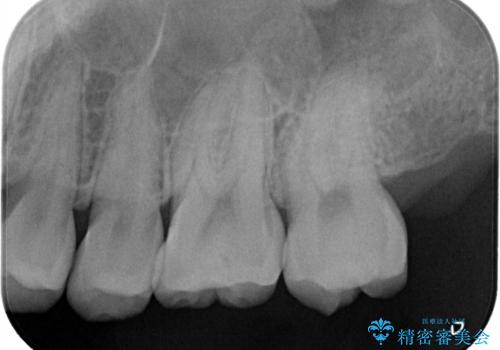

- 定期検診で虫歯が見つかった患者様です。ハイブリッドインレーで治療を行いました。

定期検診で虫歯が見つかった患者様です。

ハイブリッドインレーで治療を行いました。

ハイブリッドインレーはセラミックインレーとは違い、セラミックとプラスチックの混合物です。保険治療の材料よりは優れていますが、プラスチックが混ざっている分、セラミックインレーには劣ります。型取りの材料はセラミックインレーの時と同様のシリコン印象材を使用しています。